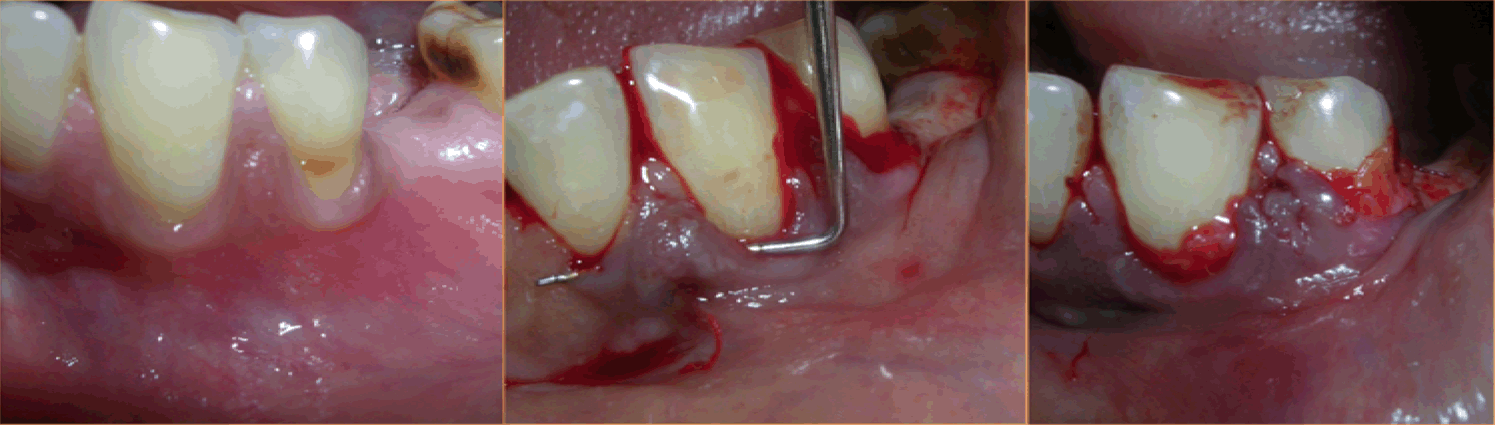

Case 1: A 36-year-old female reported with the chief complaint of sensitivity in lower right posterior teeth. On examination there was Millers Class III recession in relation to 44 and 45 (Figure 1). The width of attached gingiva was found to be inadequate since the tension test was positive. After phase I therapy, a pouch and tunnel technique utilizing a connective tissue graft was planned for root coverage. A sulcular incision was made through each recession area and the tissues gradually undermined including the base of the interdental papilla without the tip and the undermining extended up to the mucogingival junction so as to relax the flap sufficiently to allow placement of the connective tissue graft. Thus gradually a pouch and tunnel was prepared connecting the recipient sites for placement of the graft (Figure 2). The connective tissue graft was harvested from the palate using Liu's Class 1a incision (Figure 3). This graft was then placed using a technique described by Zabaluigi et al. where two resorbable sutures of different colors were placed, one on either side of the graft. Using these sutures, the graft was gradually manipulated into the pouch and through the tunnel to cover the adjacent recipient sites. Once the graft was completely inside the tunnel, it was positioned coronal to the cemento-enamel junction. The ends were sutured with a simple square knot (Figure 4). A periodontal pack was placed both at the recipient site as well as the donor site using an acrylic stent for the palatal placement.

Figure 1: Millers Class III recession in relation to 44 and 45 (Case 1).

Figure 2: Pouch and tunnel preparation (Case 1).

Figure 3: The connective tissue graft was harvested from the palate using Liu's Class 1a incision.

Figure 4: The graft placed into the tunnel and sutured.